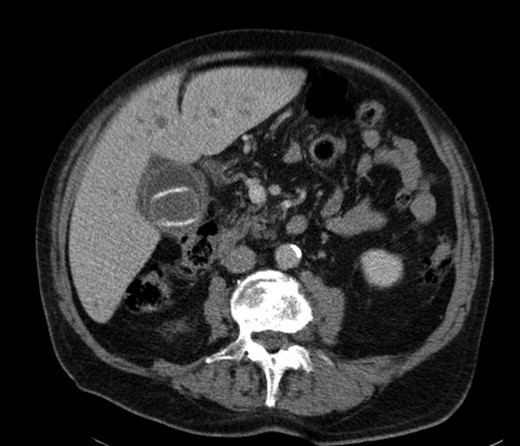

A 92-year male, with no significant co-morbidities apart from peptic ulcers, was admitted with 6 days of obstination. On examination he was dehydrated, with a hugely distended abdomen but no signs of peritonitis. Blood showed features of dehydration and plain abdominal X-ray demonstrated both small and large bowel dilatation, but no obvious causal pathology. A contrast-enhanced computed tomography scan revealed a 2.5-cm partially calcified gallstone impacted at the descending colon-sigmoid junction (Fig. 1). There was no stricture or diverticular disease distal to the stone. A cholecysto-colic fistula could be seen (Fig. 2), with a further smaller gallstone in the caecum (Fig. 3). The offending gallstone could be seen incidentally in the gallbladder on imaging 3 years previously (Fig. 4).

Cholecysto-colic fistula, with a thick-walled, dilated, gallbladder.